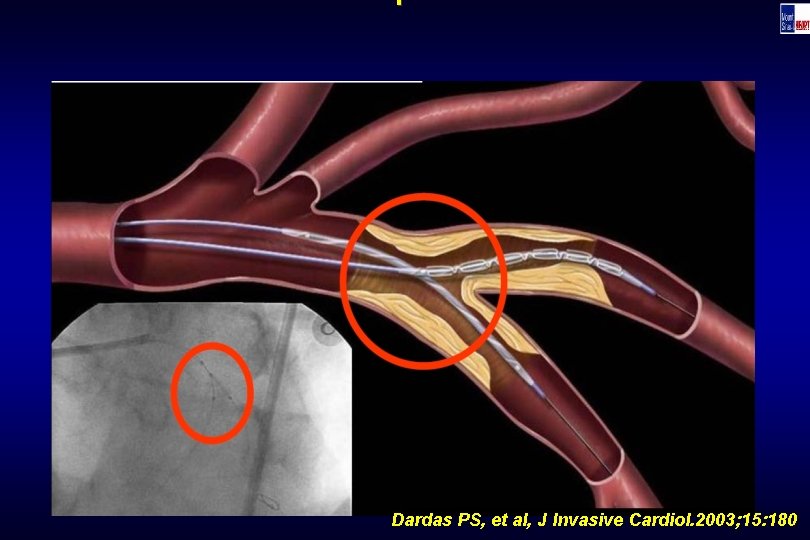

Technique Dardas PS, et al, J Invasive Cardiol. 2003; 15: 180

Technique Dardas PS, et al, J Invasive Cardiol. 2003; 15: 180

Technique Dardas PS, et al, J Invasive Cardiol. 2003; 15: 180

Technique Dardas PS, et al, J Invasive Cardiol. 2003; 15: 180

Technique Dardas PS, et al, J Invasive Cardiol. 2003; 15: 180

Technique Dardas PS, et al, J Invasive Cardiol. 2003; 15: 180